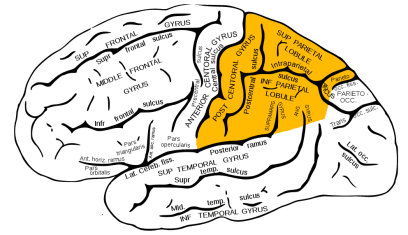

The incisura preoccipitalis cuts into the upper convexity of the brain hemispheres. As a result, the gyrus postcentralis, in which there are sensory centers, belongs to the parietal lobe. There are two curves in the lower area of the parietal lobes. Those are the anterior, gyrus supramarginalis and posterior, gyrus angularis.

枕前切口切入大脑半球的上凸部。因此,感觉中枢的中央后回属于顶叶。顶叶下部有两条曲线。它们分别是前、边缘上回和后、角回。

Now, we will elaborate on anatomical parts of the parietal lobe about their specific functions. First of all, the postcentral gyrus of the parietal lobe (the primary somatosensory region) processes somatic sensory stimuli that serve to recognize the shape, composition, and weight of an object.

我们将详细阐述顶叶的解剖学部分。首先,顶叶中央后回(初级躯体感觉区)处理躯体感觉刺激,这种刺激有助于识别物体的形状、组成和重量。

The spatial organization center also applies to the primary somatosensory cortex located in the anterior portions of the parietal lobe. The somatosensory functions of one side of the body are controlled by the contralateral hemisphere of the brain.

空间组织中心位于顶叶前部的初级躯体感觉皮层。身体一侧的躯体感觉功能由大脑的对侧半球控制。

The posterolateral areas of the parietal lobe are responsible for creating visual and spatial information, that is, for trajectory information of moving objects. These areas are also responsible for proprioception (awareness of the position of body parts in space).

顶叶的后外侧区域负责产生视觉和空间信息,即运动物体的轨迹信息。这些区域也负责本体感觉(意识身体部位在空间中的位置)。

In the dominant hemisphere, the Gerstmann area located in the central part of the parietal lobe is responsible for the ability to compute, write, properly perceive space, especially the left-to-right orientation, and for finger recognition.

在优势半球中,位于顶叶中央的Gerstmann区域负责计算,书写,正确感知空间,尤其是从左到右的方向,以及手指识别的能力。

The nearby angular gyrus is responsible for naming things and other aspects of word recognition. The non-dominant parietal lobe participates in the integration of the contralateral side of the body into space and is responsible for navigating in the space.Finally, it plays an important role in different abilities such as drawing.

附近的角回负责命名事物以及单词识别的其它方面。非优势顶叶参与身体对侧的整合进入空间,并负责在空间导航。最后,它在绘画等不同能力中起着重要作用。

Furthermore, the posterior central gyrus houses the centers of sensitivity are projected with a projection of the body similar to that of the anterior central gyrus. A human face is projected in the lower third of the gyrus. The middle third segment projects a hand, while the foot is projected in the upper third part.

In the upper parietal gyrus, there are centers in charge of complex types of deep sensitivity: musculoskeletal, two-dimensional spatial sensation, sense of weight and volume of movement, sense of object recognition to the touch. The posterior to upper portions of the posterior central gyrus contain localized centers, providing the ability to identify one’s body, its parts, their proportions, and their relative position.

在顶上回,有一些中枢负责复杂类型的深度敏感: 肌肉骨骼、二维空间感觉、重量感和运动量感、对触觉的物体识别感。后中央回的后至上部分包含局部中枢,提供辨认身体、部位、比例和相对位置的能力。

The most important sensory area is the parietal cortex segment of the postcentral gyrus. In addition, its corresponding part of the paracentral lobe plays a very important sensory role. These zones are called somatosensory region I.

最重要的感觉区域是中央后回的顶叶皮层部分。此外,其对应的旁中心叶部分起着非常重要的感觉作用。这些区域被称为躯体感觉区I。

In addition to the somatosensory region I, there is a smaller size region called the somatosensory area II, located at the intersection of the central sulcus with the upper edge of the temporal lobe, at the depth of the lateral sulcus. The degree of localization of body parts is less pronounced.

除了躯体感觉区I之外,还有一个较小的区域称为躯体感觉区 II,位于中央沟与颞叶上缘的交叉处,在外侧沟的深处。身体部位的定位程度不太明显。